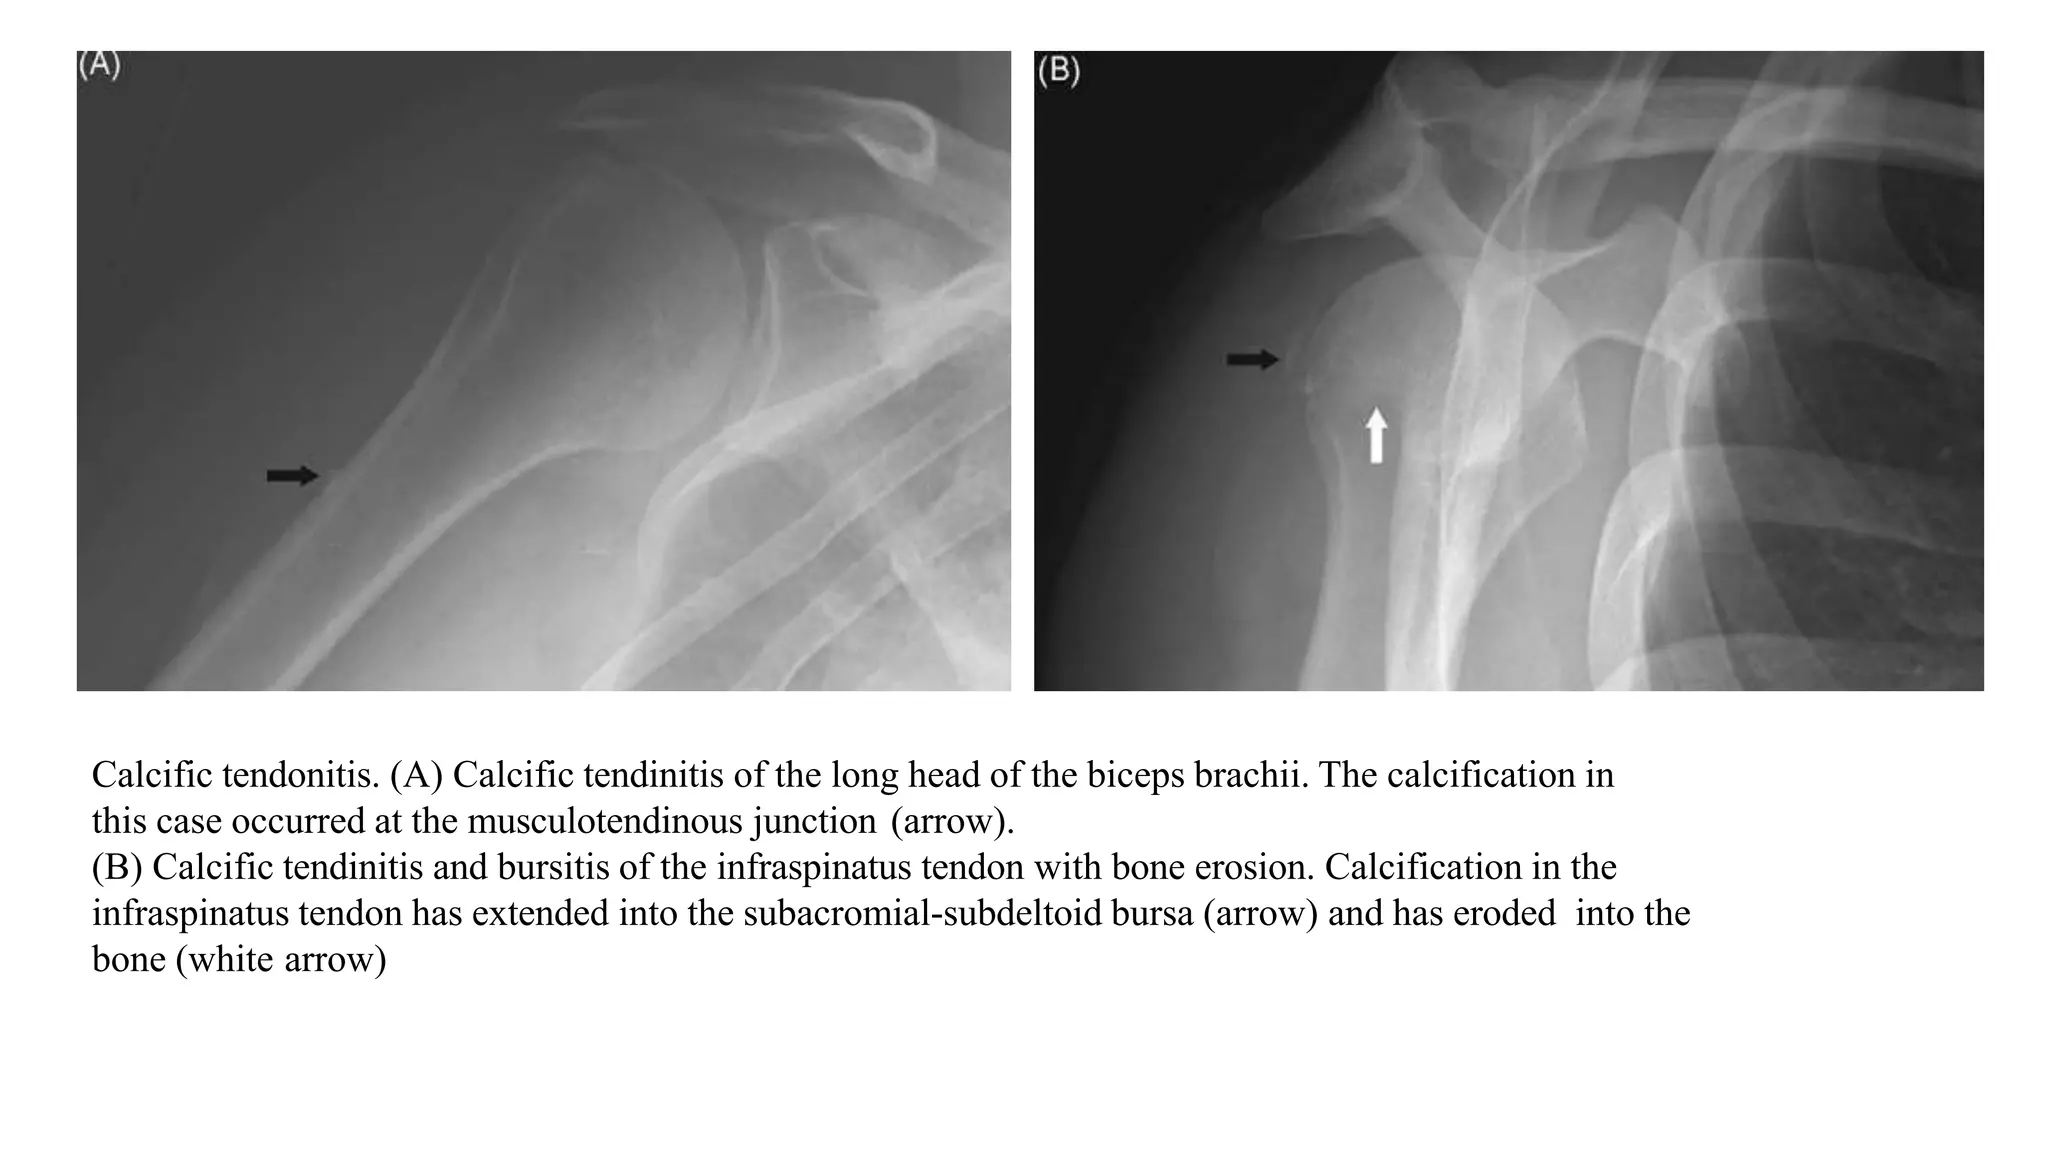

Calcific tendonitis. (A) Calcific tendinitis of the long head of the biceps brachii. The calcification in

this case occurred at the musculotendinous junction (arrow).

(B) Calcific tendinitis and bursitis of the infraspinatus tendon with bone erosion. Calcification in the

infraspinatus tendon has extended into the subacromial-subdeltoid bursa (arrow) and has eroded into the

bone (white arrow)